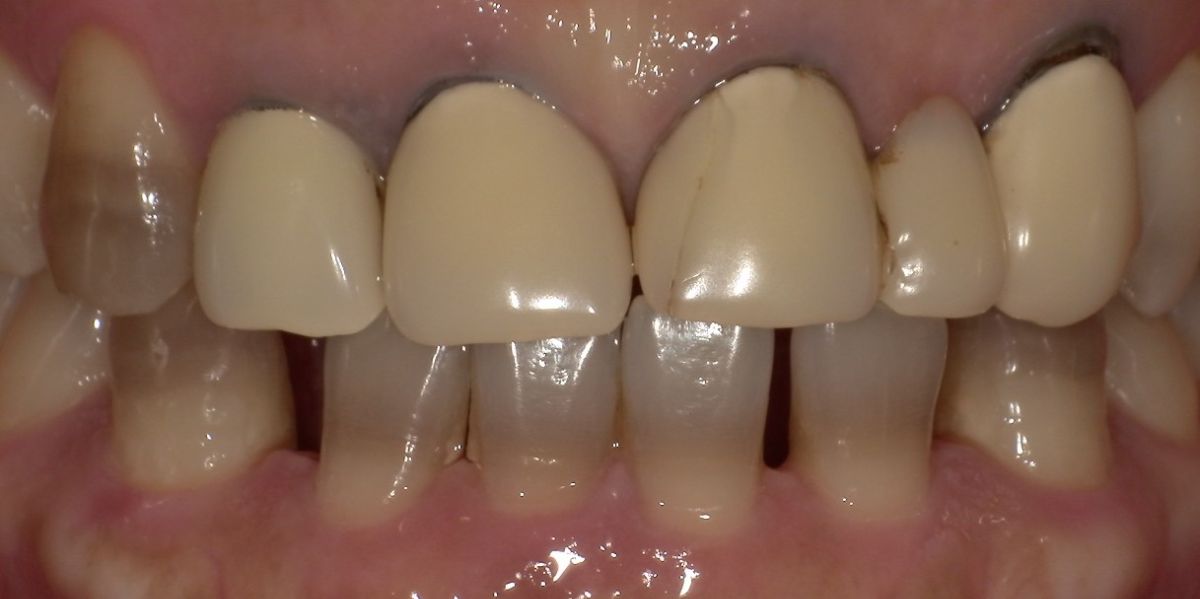

-

主訴:上の前歯の黒ずみが気になるセラミックで治したい

上部構造:すべてフルジルコニア

費用:¥1,100,000

治療期間:2ヶ月

副作用・リスク:特に前歯部は色合わせに何度かつくりかえが必要な場合があります。歯周病、う蝕、根の治療が必要な場合はさらに時間がかかります。